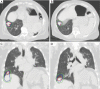

Lung motion with and without abdominal compression. Axial (A,B) and coronal (C,D) CT images of a patient with a right lower lobe stage I non-small cell lung cancer planned for SBRT with contours after CT simulation of GTV (red), iGTV (blue) and PTV (green). (A,C) CT simulation without motion mitigation; (B,D) CT simulation with abdominal compression. SBRT, stereotactic body radiation therapy; GTV, gross tumor volume; iGTV, internal GTV; PTV, planning target volume; CT, computed tomography.